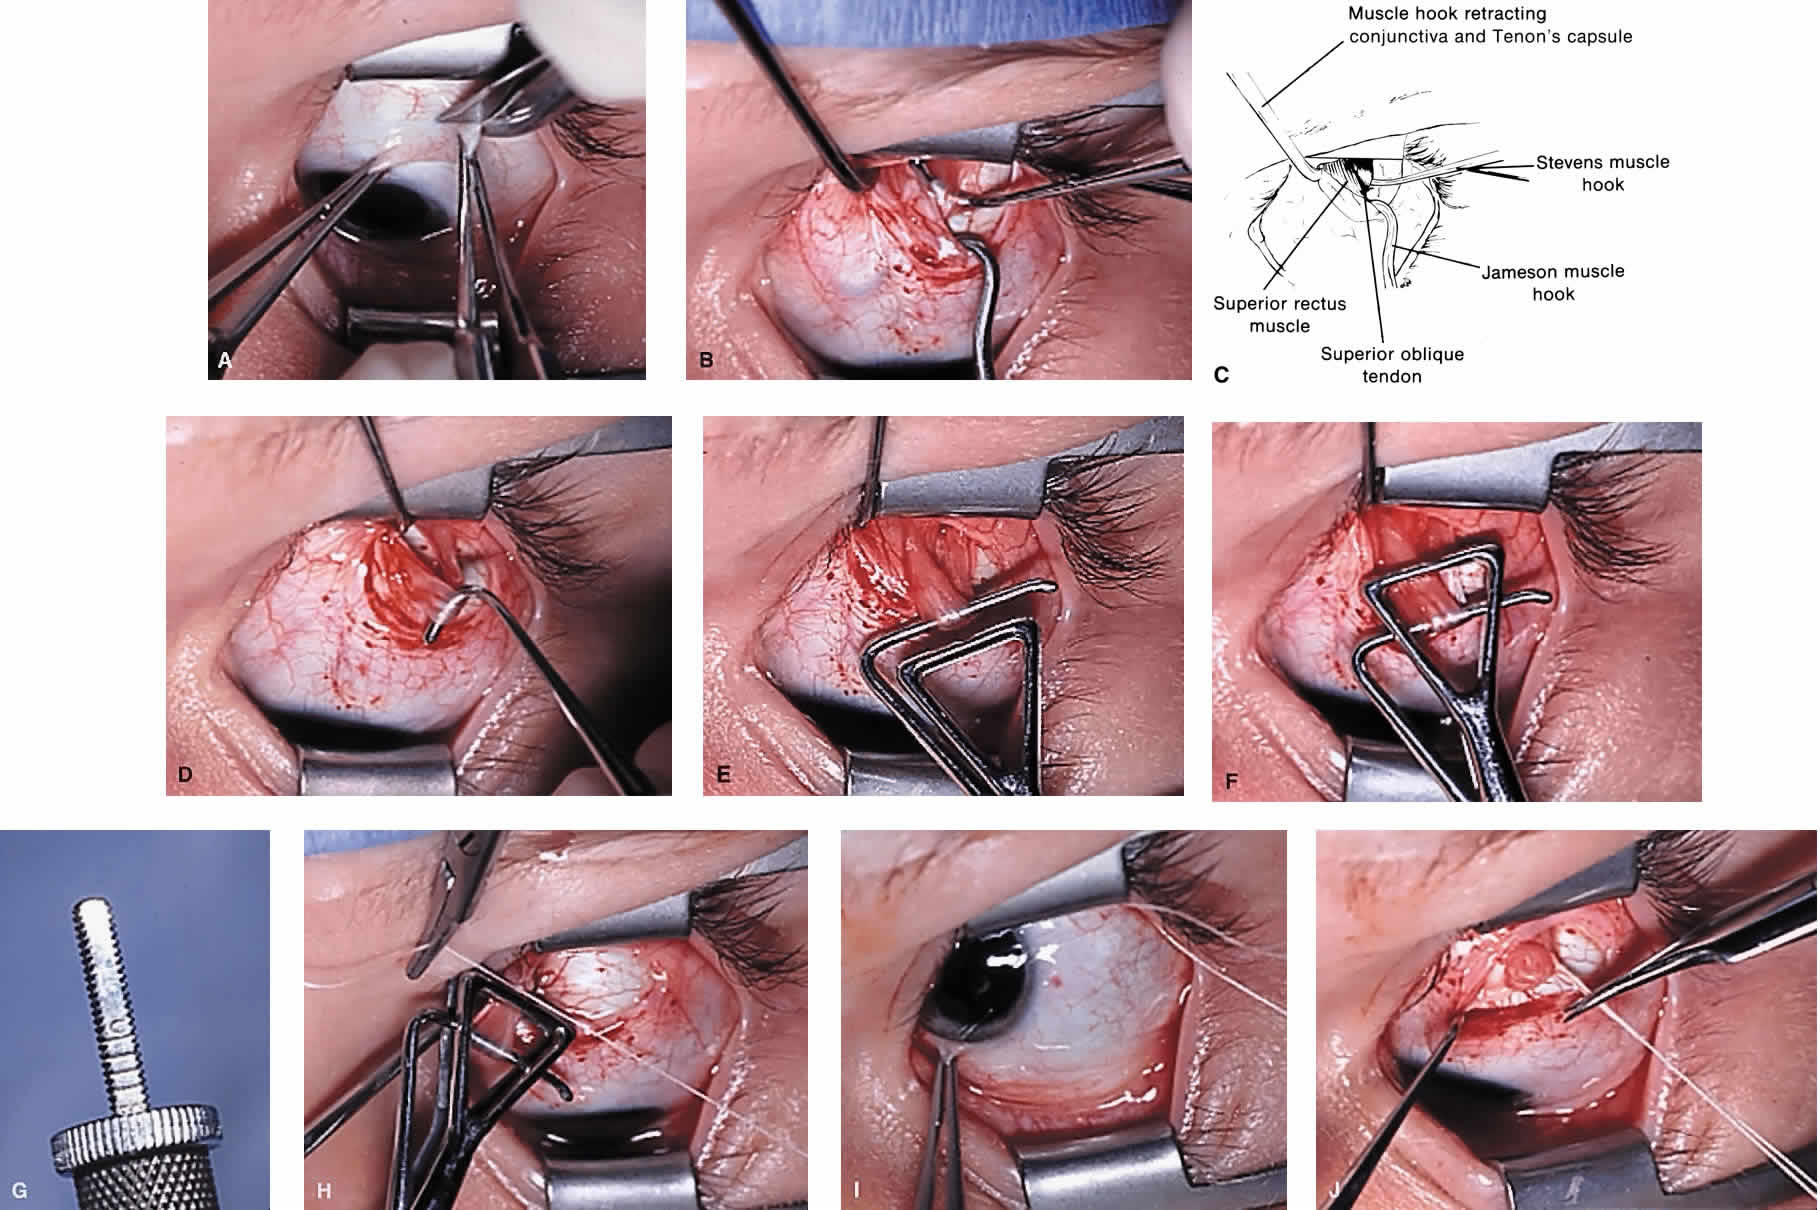

The superior oblique tendon tuck is best performed near the tendon's insertion as described by McLean.48 The surgical procedure is performed through a superior temporal cul-de-sac approach (Fig. 4). With the globe depressed, an incision is made through the conjunctiva and Tenon's fascia just temporal to the lateral border of the superior rectus muscle and parallel to the corneoscleral limbus. The superior rectus muscle is engaged on a muscle hook and the globe adducted and positioned in maximal depression. The lateral rectus muscle may also be used to assist positioning the globe. Using two small muscle hooks, the conjunctival incision is stretched open posteriorly in a triangular fashion. The lateral border of the superior rectus muscle is elevated and displaced medially. The globe is then examined for the glistening, white fibers of the superior oblique tendon running flush against the sclera and directed anteromedially. The anterior portion of the reflected tendon typically inserts under the lateral border of the superior rectus muscle, 5 to 7 mm posterior to its insertion. However, this location may vary, and anatomic anomalies are common (Fig. 5).12,37,47,48 The superior oblique tendon looks very different near its scleral insertion than 10 mm more proximally, where it becomes cordlike and enters Tenon's fascia after passing under the belly of the superior rectus muscle. Inexperienced surgeons have mistaken the lateral portion of the tendinous insertion of the superior rectus muscle for the superior oblique tendon (Fig. 6).49 However, the superior rectus muscle travels toward the orbital apex and contains prominent anterior ciliary blood vessels, whereas the superior oblique tendon is directed toward the trochlea and is usually avascular. In addition, direct traction on the superior oblique tendon can easily be palpated at the trochlea by pressing a finger over the eyelid in the superior nasal quadrant of the orbit.10 This is a reliable sign that the tendon (and not some other structure) has been engaged on the muscle hook.

After the superior oblique tendon has been positively identified, it is gathered on a Stevens tenotomy or other muscle hook with a small tip. This maneuver is most readily accomplished by passing the hook over the tendon with its tip parallel to the sclera and pointed medially. Direct visualization of the tendon is essential, in that blind sweeping can be hazardous. A superior temporal vortex vein usually exists near the posterior insertion of the superior oblique tendon and the optic nerve is within reach. In addition, it is important to avoid passing the muscle hook into orbital fat because its release into the sub-Tenon's space predisposes the eye to develop an adherence syndrome postoperatively.50

The superior oblique tendon is drawn forward through the surgical wound and attachments to Tenon's fascia and the superior rectus muscle are cut. A second pass of the muscle hook helps ensure that no fibers have been missed. Gross assessment of tendon laxity is then performed. A lax tendon requires a greater amount of tuck, whereas a normal tendon should be approached with caution, and a taut tendon should not be shortened at all. A Bishop tendon tucker is helpful to control the isolated tendon and permits the surgeon to quantitate the amount of tendon shortening conveniently. The tendon is drawn in the tucker until snug, but not tight. The loop of tendon is then sewn to itself using a nonabsorbable suture such as 5-0 braided Dacron. After this provisional tuck has been completed, the tendon is released into the orbit and a traction test is performed with the eye positioned in maximum adduction. It has been our experience that the ideal tuck results when the amount of tendon shortening produces its first resistance to elevation as the inferior limbus crosses an imaginary line between the medial and lateral canthus (Fig. 7).34,51 Care must be taken not to retropulse the globe into the orbit, because this exaggerates the duction limitation. An average tendon shortening of approximately 12 mm is required in congenital superior oblique muscle palsy (lax tendon) and 8 mm in acquired palsy (normal tendon). However, the optimum amount of tuck does not necessarily correlate with the size of the hypertropia in primary gaze position and intraoperative titration is essential. If the initial tuck is too tight or too loose based on results of traction testing, the tendon is retrieved from the orbit and the tuck is adjusted. The final tie-off is performed by passing the suture through and around the superior oblique tendon a second time after which it is tied securely. This minimizes the potential for tendon slippage through the tuck and provides additional security should a suture loop fail postoperatively. It is not necessary to sew the redundant tendon to the sclera. Conjunctival closure is performed at the surgeon's discretion. A running suture of 6-0 plain catgut is well tolerated and prevents the conjunctiva from gaping open postoperatively.

To perform the classic Harata-Ito procedure, the superior oblique tendon is identified and isolated on a muscle hook in a fashion similar to a superior oblique tendon tuck (see previous discussion). A small muscle hook is used to separate between one third and one quarter of the most anterior tendon fibers for approximately 8 to 10 mm from their scleral insertion. A nonabsorbable, double-armed suture, such as 5-0 braided Dacron, is passed through the tendon defect and then through the sclera adjacent to the superior border of the lateral rectus muscle posterior to its scleral insertion. When the suture is secured to the sclera, the anterior fibers are advanced and anteriorly transposed to create a new functional insertion. The surgical effect can be titrated by altering both the tension and position of the suture using an intraoperative adjustment technique in cooperative patients or fundus examination under general anesthesia.56 Postoperative overcorrection can easily be addressed by cutting the scleral suture. If performed during the first several days after surgery, the transposed fibers of superior oblique tendon return to their normal anatomic position.